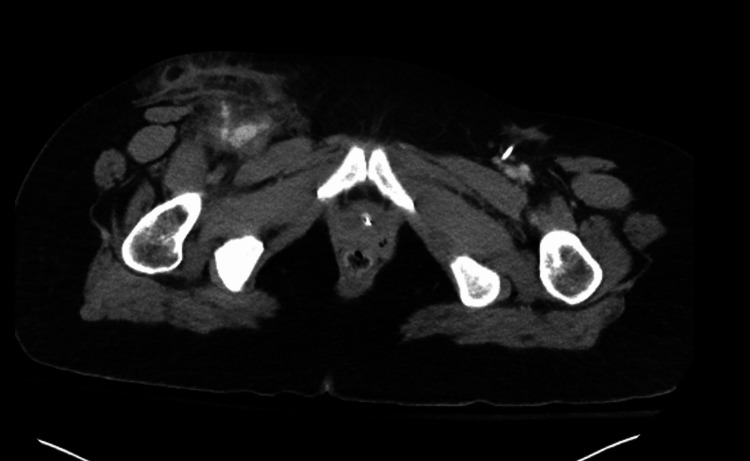

To address the cerebral edema identified on the CT brain scan, the patient received 3% hypertonic saline at a rate of 30 cc/h, alongside escalated pressor support. A CT abdominal imaging also showed an irregularity within the right groin, possibly indicating a pseudoaneurysm or hematoma (Figure 4). Despite these interventions, the significant cerebral edema and hypoxic injury prompted a consultation with neurosurgery, who deemed invasive interventions unlikely to improve the prognosis. Consequently, palliative care discussions ensued, culminating in a mutual decision with the family to transition the patient to a do-not-resuscitate (DNR) status. Sedation was discontinued on the second day of admission, leading to a brain death evaluation revealing no evidence of brain activity in the early afternoon. A repeat evaluation was scheduled for the following day, during which sedation remained off, and no clinical changes were observed. Another brain death evaluation, including an apnea challenge, confirmed the absence of brain activity on the third day. With the family present, mechanical and chemical support was withdrawn, with the patient entering asystole shortly thereafter, and the time of death was recorded on day three of admission, approximately 79 hours after arrival to the ED. The final diagnoses encompassed multiple contributing factors, including cardiac arrest secondary to drug overdose, accidental drug overdose, cocaine use disorder, acute respiratory failure with hypoxia and hypercapnia, anoxic brain injury, transaminitis, metabolic acidosis, acute kidney injury, and cerebral edema secondary to anoxia.